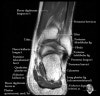

- Coronal section

The coronal oblique T1 sequence follows the tendons of the ankle around the malleolar turns and also evaluates the medial ankle ligaments.

The coronal oblique PD fat suppressed sequence follows the tendons of the ankle around the malleolar turns and is particularly important in evaluation of the Posterior tibialis tendon.

Bone and marrow

Talar dome

Deltoid ligament

Tendons in arch

Plantar fascia

Troubleshoot ligaments